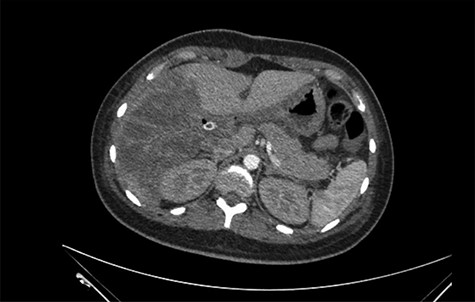

She was referred to our center on postoperative Day 4 due to progressive jaundice and encephalopathy. A triphasic contrast-enhanced abdominal computed tomography (CT) was done revealing a right liver lobe infarct, absence of the right and left hepatic arteries (Fig. 1), presence of an accessory left hepatic artery from the left gastric artery (Fig. 2) and right portal vein thrombosis with extension to the main portal vein (Fig. 3).

Right liver lobe necrosis and absence of proper hepatic artery on the arterial phase of the triphasic contrast-enhanced abdominal CT.